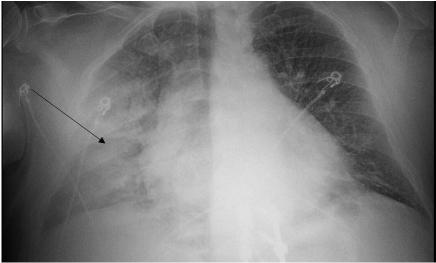

The patient’s abdomen was diffusely tender on palpation with voluntary guarding and no rebound or distention. He did not have any costovertebral angle tenderness. He was tender to palpation in the bilateral groin and scrotal regions with purpura, desquamation, warmth, and edema. No lymphadenopathy was noted. His rectal tone was intact with no evidence of urinary retention on bladder ultrasound. His bilateral lower extremities and back were tender on palpation with full range of motion, 5/5 strength, and no signs of trauma or edema. Sensation was diffusely decreased in the bilateral lower extremities. Nonblanching purpura was noted on his lower extremities and dorsal aspect of his hands. Bullae and desquamation were also present on his lower extremities with a positive Asboe-Hansen sign and negative Nikolsky sign (Image 1). There was no rash involvement of his face, torso, or mucosal membrane.

1. Rash on a 51-year-old male who presented with back pain, lower extremity numbness, and a progressive purpuric rash.

(A) Desquamation (white arrow), non-blanching purpura and hemorrhagic bullae (black arrow) on the bilateral lower extremities.

(B) Non-blanching purpura (black arrows) on the bilateral dorsal hands and bilateral legs.

An extensive workup was initiated by the team including blood, urine, and multiple imaging studies. Some key findings from this workup included elevated blood urea nitrogen and creatinine, elevated creatine kinase levels, a bandemia, thrombocytopenia, and a D-dimer level that was greater than the upper limit that the laboratory could report. The ECG showed sinus tachycardia but was otherwise non-diagnostic. He had a chest radiograph, which did not reveal any infiltrates, pneumothorax, or effusions. Computed tomography was apparently not revealing of surgical pathology, and the normal ABI testing lessened the likelihood of acute vascular compromise.

radiography (Image 3) and computed tomography (CT) with contrast of the cervical, thoracic, and lumbar spine, and of the chest, abdomen, and pelvis were also completed but did not demonstrate any acute abnormalities to explain the patient’s symptoms. Bilateral lower extremity ankle brachial indices (ABI) were normal. Ultimately, a diagnostic test was performed that confirmed the diagnosis.